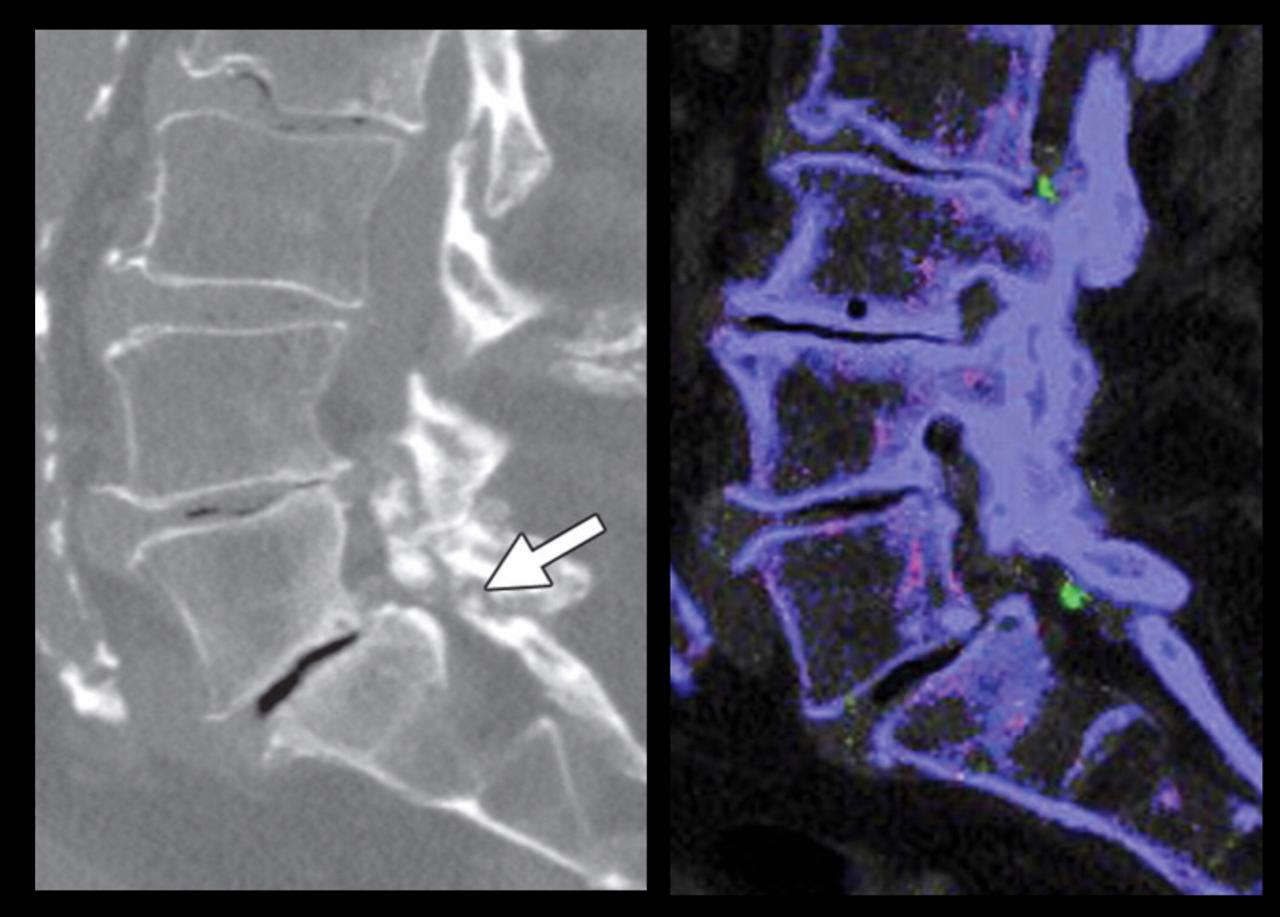

The fluid sign is one of the radiological features of osteoporotic fractures, and can be helpful in distinguishing them from metastatic vertebral fractures, as it is seen more often in osteoporotic fractures and is rarely seen in metastatic fractures.

The exact pathogenesis is not known, although proposed mechanisms include spontaneous avascular necrosis of the vertebral body (or Kümmell disease) or osteonecrosis at the site of an acute insufficiency vertebral fracture.

In fractured vertebral bodies, the fluid sign was adjacent to the fractured end plates and exhibited signal intensity isointense to that of cerebrospinal fluid on a background of diffuse hyperintensity in the vertebral body because of acute collapse.

It is seen in acute vertebral compression fractures that show bone marrow edema. In osteoporotic fractures, the fluid sign was significantly associated with fracture severity.